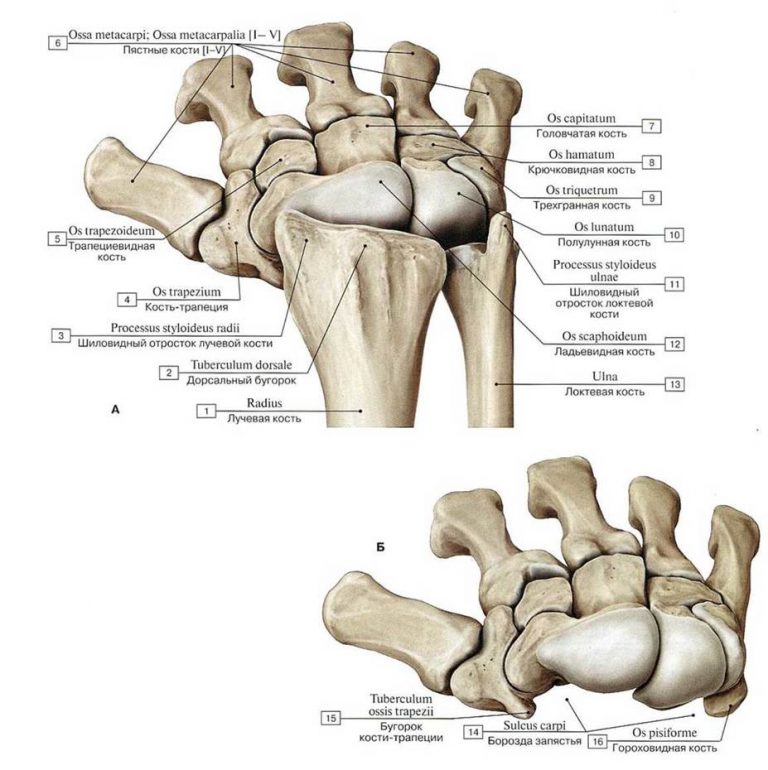

Анатомия кисти руки и строение костей